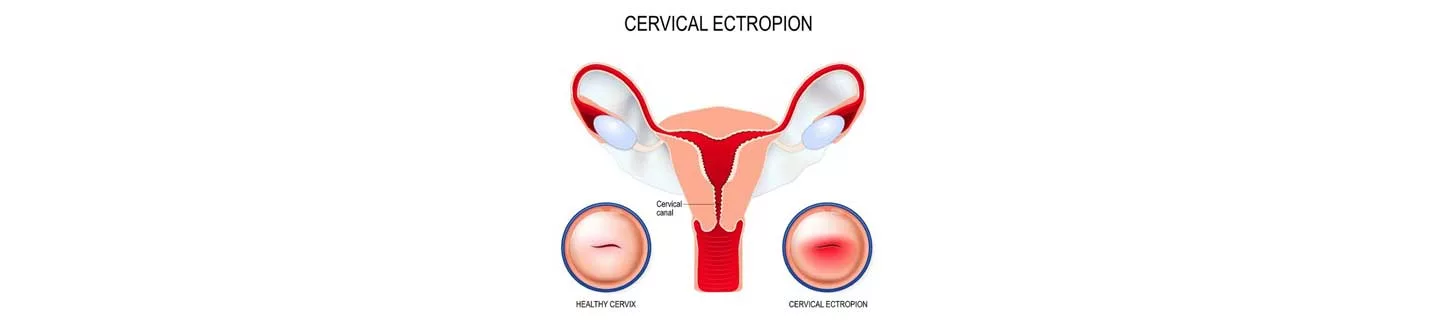

Lộ tuyến cổ tử cung là một tình trạng đơn giản, thường gặp, không gây ung thư ở phụ nữ và xảy ra khi các tuyến nằm bên trong cổ tử cung (ống cổ tử cung của tử cung) chuyển dịch quay ra ngoài làm lộ biểu mô trụ bên trong ra môi âm đạo có tính axit. Biểu mô tuyến bị lộ ra ngoài có bề mặt màu đỏ và có thể được bao phủ bởi một chất dịch màu vàng đục.

Lộ tuyến cổ tử cung còn được gọi là xói mòn cổ tử cung, đây là một thuật ngữ không đầy đủ vì nó ngụ ý rằng các tế bào lót mịn bên ngoài đã bị xói mòn để lộ mô bên dưới. Mặc dù điều này có thể xảy ra, nhưng phần lớn các “xói mòn” đại diện cho các khu vực của cổ tử cung – nơi các tế bào vảy bên ngoài đã được thay thế đơn giản bằng sự phát triển quá mức của biểu mô tuyến bên trong.

Ngày nay, những lý thuyết này đã mất đi vị thế khi các chuyên gia tin rằng hiện tượng lộ tuyến cổ tử cung là một hiện tượng giải phẫu bình thường mà một số phụ nữ bị lộ tuyến cổ tử cung bẩm sinh. Hơn nữa, các nhà nghiên cứu đã chỉ ra rằng đôi khi nguyên nhân là sự gia tăng nồng độ estrogen trong cơ thể, điều này có thể thay đổi hoặc điều chỉnh cổ tử cung ở điều kiện bình thường như trong lứa tuổi vị thành niên hoặc sau đó, trong khi mang thai hoặc sử dụng thuốc tránh thai.

Ở phụ nữ đã sinh đẻ, biểu mô ống cổ tử cung có thể được nhìn thấy không liên tục. Lỗ ngoài cổ tử cung mở rộng và loe ra là kết quả của những thay đổi từ lần chuyển dạ và sinh trước đó.